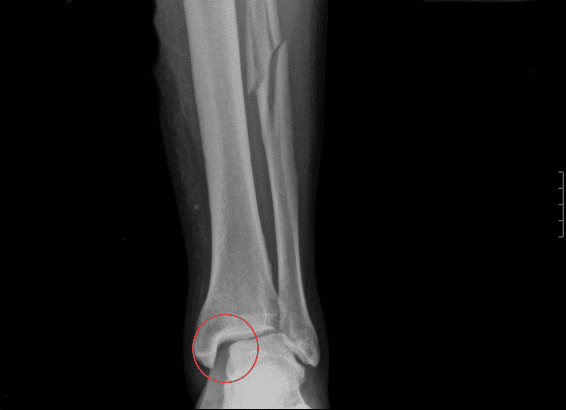

Рентгеновские снимки перелома Мезоннева